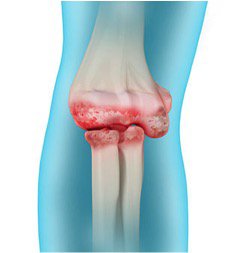

• воспалительные процессы — артриты различного происхождения;

• дегенеративные заболевания — артроз, который постепенно разрушает хрящевую ткань;

Методы лечения